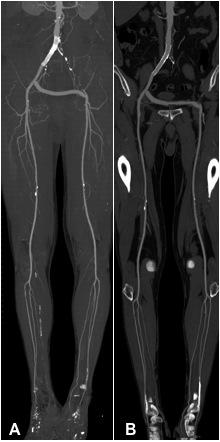

Abbildung:

Die Abbildungen A und B zeigen einen 74-jährigen Mann nach Stentimplantation in die rechte Beckenarterie sowie Anlage eines cross-over-Bypass von rechts nach links bei Verschluss der linken Beckenarterien.

Abb. A zeigt eine MIP-Darstellung der CT Angiographie der Becken-Bein-Arterien. Bei guter Übersichtlichkeit ist der Stent in der rechten Beckenarterie nicht zu beurteilen.

In der nur an unserer Abteilung verfügbaren MultiPath-CPR (Abb. B) kann in den Stent hineingeschaut werden. So kann man beurteilen, ob eine Instent-Restenose vorliegt.